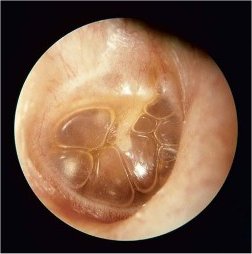

Cholestéatome : Le Cholestéatome (otite moyenne chronique suppurée): Traitement des symptômes, des conseils et aider les

A propos de cholestéatome (otite moyenne chronique suppurée)

Le Cholestéatome est une maladie de l'oreille, qui est un organe de l'ouïe et le maintien de l'équilibre. L'oreille est divisée en plusieurs parties à savoir l'oreille externe (pavillon), canal de l'oreille qui rejoint l'oreille externe à l'oreille moyenne, l'oreille moyenne et l'oreille interne.

Comme son nom l'indique, l'otite moyenne chronique suppurée est une infection de longue date, qui peut entraîner un problème grave de l'oreille appelé cholestéatome. Le cholestéatome est une forme d'otite chronique avec présence d'épithélium pavimenteux stratifié dans l'oreille moyenne. Cet épithélium desquame et se kératinise (structure histologique de la peau), et peut provoquer l'érosion voire la destruction des structures contenues dans et autour de l'oreille moyenne.

Signes et symptômes de cholestéatome (otite moyenne chronique suppurée): Diagnostic

Le Cholestéatome est une affection de plus en plus bénigne et lente, fournissant ainsi suffisamment de temps pour être diagnostiquée tôt dans l'évolution de la maladie. Les symptomes comprennent des douleurs dans l'oreille malade, avec un écoulement pouvant être nauséabond. Le Cholestéatome peut endommager les osselets de l'oreille moyenne, provoquant ainsi une rupture dans la conduction du son. Ceci se manifeste par une perte d'audition dans l'oreille affectée. Dans certains cas avancés, la croissance du cholestéatome peut envahir l'oreille interne et endommager les canaux semi-circulaires, résultant en des étourdissements, déséquilibres ou vertiges.

Il est conseillé de consulter un spécialiste

qui examinera l'oreille malade. Le scanner ou l'IRM peuvent également aider à établir le diagnostic.

Certains Cholestéatomes peuvent être présents depuis la naissance, mais de tels cas sont rares. Il est le plus souvent une complication d'une infection de longue date de l'oreille moyenne.

La croissance cholestéatome peut progresser à empiéter sur le nerf facial qui passe à côté de l'oreille. Cela peut entraîner une paralysie faciale et se manifeste par la descente de la face et l'incapacité à fermer un des deux yeux. D'autres complications qui peuvent être rencontrés comme l'abcès cérébral, la méningite ou la surdité d'une oreille.

Le Cholestéatome est une maladie soignable et l'intervention chirurgicale est le traitement de choix. La résection chirurgicale de la croissance de cholestéatome suivie par mastoïdectomie contribue à l'amélioration de la perte auditive dans une majorité des cas. Il est conseillé de consulter périodiquement le spécialiste, afin de détecter toute rechute possible.